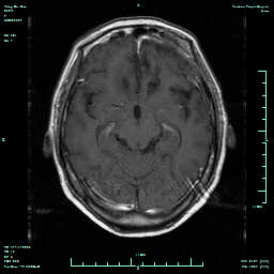

张剑平治疗组在全麻下行左侧眶上外侧入路行肿瘤切除术,手术顺利,术后10天拆线。出院时患者无神经功能障碍。术后1个月复查,患者言语流利,肢体功能良好,认知能力明显改善,复查MRI提示肿瘤全切。

术后1月再次复查颅脑MRI增强